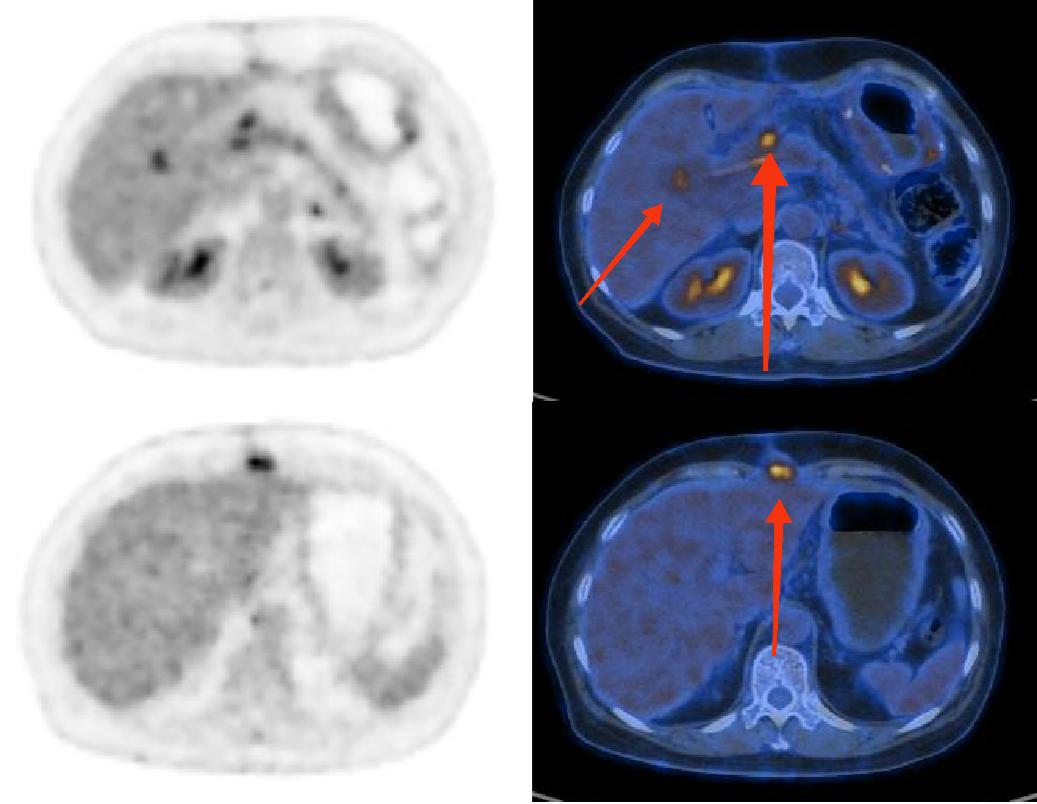

图为18F-FDG PET及PETCT图像。上图两枚红箭头所指为胰十二指肠切除术后吻合口处高代谢病灶,不能完全排除是否为肿瘤术后复发病灶;下图红箭头所指为切口皮下高代谢软组织灶,不能完全排除是否为肿瘤转移灶。

PET/CT作为作为分子影像诊断的“先锋”,可以通过核素标记特殊的“分子探针”显像剂,来显示全身各处的病灶。18F-FDG PET/CT是非特异肿瘤的显像方法,适用于所有肿瘤(包括NEN),但18F-FDG对于神经内分泌肿瘤的诊断价值有限,病灶摄取18F-FDG的程度与Ki-67指数(一种病理标记物)相关,而奥曲肽对于神经内分泌肿瘤的特异性非常高,如果将神经内分泌肿瘤比较为“锁”,那么奥曲肽就是专门打开这把锁的“钥匙”,可以明确内分泌肿瘤是否存在多发、判别复发及隐匿性微小神经内分泌肿瘤。临床上,通常将18F-FDG PET/CT与奥曲肽PET/CT双核素显像联合应用,互相补充以全面评估神经内分泌肿瘤。

捷克论坛 PET影像中心进行的第一例18F-奥曲肽PET/CT显像应用于一名55岁的女性患者,一个多月前因胰腺内分泌肿瘤进行了胰十二指肠切除术,现继续就诊于捷克论坛 肿瘤科,临床医生为了明确病情,为其申请了18F-奥曲肽PET/CT显像,期望能更好地给予患者个性化治疗方案。在PET影像中心毛志群主任的带领下,PET影像中心的医护人员全心全意为患者服务,并成功帮助患者及临床医生完善了诊疗方案。